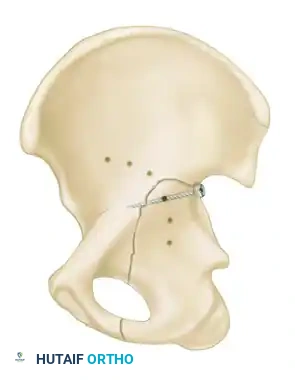

Incarcerated Intra-Articular Fragments

Following the closed reduction of a hip dislocation, a post-reduction CT scan is mandatory. While small avulsions of the ligamentum teres sequestered deep in the cotyloid fossa may be observed, any osteochondral fragment lodged between the articulating surfaces of the femoral head and the acetabular dome necessitates urgent surgical excision and joint irrigation.

1. Percutaneous Fixation: Limited column fixation using percutaneous fluoroscopic techniques to prevent gross displacement, allowing the fracture to heal in a stable position prior to a delayed Total Hip Arthroplasty (THA).

2. Acute Total Hip Arthroplasty: Primary THA combined with limited internal fixation (to stabilize the acetabular shell) is increasingly advocated for elderly patients with poor prognostic fracture patterns, allowing immediate full weight-bearing.